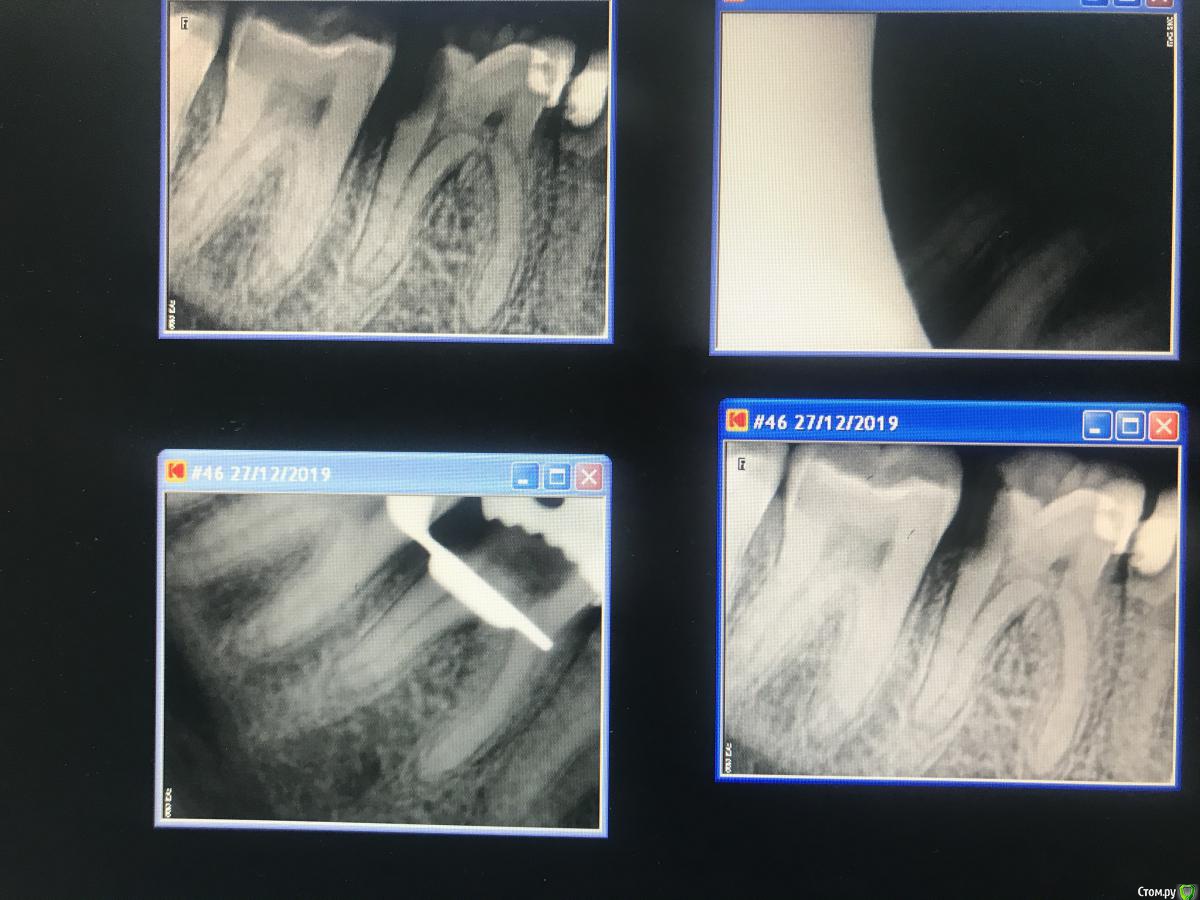

Lina112233 Опубликовано 2 января, 2020 Поделиться Опубликовано 2 января, 2020 (изменено) Здравствуйте! Я начинающий врач-терапевт стоматолог, сегодня пришла пациентка с острой болью(пульпит) з46 , я поставила мандибулчрную анестезию, инфильтрацию, но когда начала вскрывать полость зуба ей резко стало больно. Дальше на вскрытые точки(примерно в области Зех устьев) ввела анестетик веутрипульпарно,но не помогло. Оставила депульпин под фум-лентой и парасепт на неделю. Подскажите, почему ей было больно и так сильно кровило,хотя даже ампутацию не смогла сделать?и какими борами лучше проводить ампутацию,чтобы не перфорировать дно? Или я уже перфорнула?? Изменено 2 января, 2020 пользователем Lina112233 Ссылка на комментарий

Sier10 Опубликовано 15 марта, 2020 Поделиться Опубликовано 15 марта, 2020 Здравствуйте. Отдельную тему создавать не стал, так как название темы было бы аналогичным) Давно читаю форум, извлёк много полезной информации здесь, за что всем старожилам большое спасибо. Последние два дня выделись для меня очень печальными. Позавчера отлатералил пульпитный 47з. В медиальной системе в обоих каналах не довёл по 2-2,5мм, была проблема с определением рабочей длины, аплок показывал 0, плюс пациент устал сидеть больше 3часов в кресле,, но это все отговорки, своей вины и глупости я не отрицаю . Недоведение я осознал уже после того как отправил пациента с запакованными каналами и временной пломбой, когда пересматривал снимки.. естественно, пациенту все объясню и перепакую (если он меня не пошлёт куда подальше), и по этому поводу меня интересует, стоит ли держать зуб на кальции перед повторным пломбированием? Пульпарную камеру раскрывал с уже наложенным кофердамом, в протоколе гипохлоран, медиальную систему активировал гуттаперчевым штифтом, дистальный канал - эндочак. Снимки на работе, завтра скину сюда, если нужно. Ссылка на комментарий

Sier10 Опубликовано 15 марта, 2020 Поделиться Опубликовано 15 марта, 2020 А вчера на распломбировке 16з, впервые нарезал перфорацию. Работал, как обычно при распломбировке, протейперами д3 и ручными файлами, используя сольвент. Мб и нёбный каналы шли хорошо, но в дб дальше устья дело не шло и в какой то момент протейпер слишком уж резво начал резать, и пациенту стало больно. Воткнул бумажный штифт - немного кровит на кончике, но в Канале гуттаперча никуда не делась. 35 н-файл в нарезанный тонель и пошли на снимок. Увидел, что у нас перфорация, немного запаниковал, положил кальций, тефлон и временная пломба. Все объяснил пациенту, отправил на микроскоп для закрытия перфорации.Я так понимаю, что при обработке в прошлый раз чрезмерно расширили и выпрямили канал, истончив его медиальную стенку? И я во время работы где то чрезмерно приложился, наверное, как раз в этом истонченном месте и сделал перфорацию, я правильно понимаю? Помогите понять причину, пожалуйста9696B58D-E577-4BB9-8E1F-C40822CEBB98.bmp6954AB4B-1B97-40B6-901B-BA4983603E7B.bmp Ссылка на комментарий